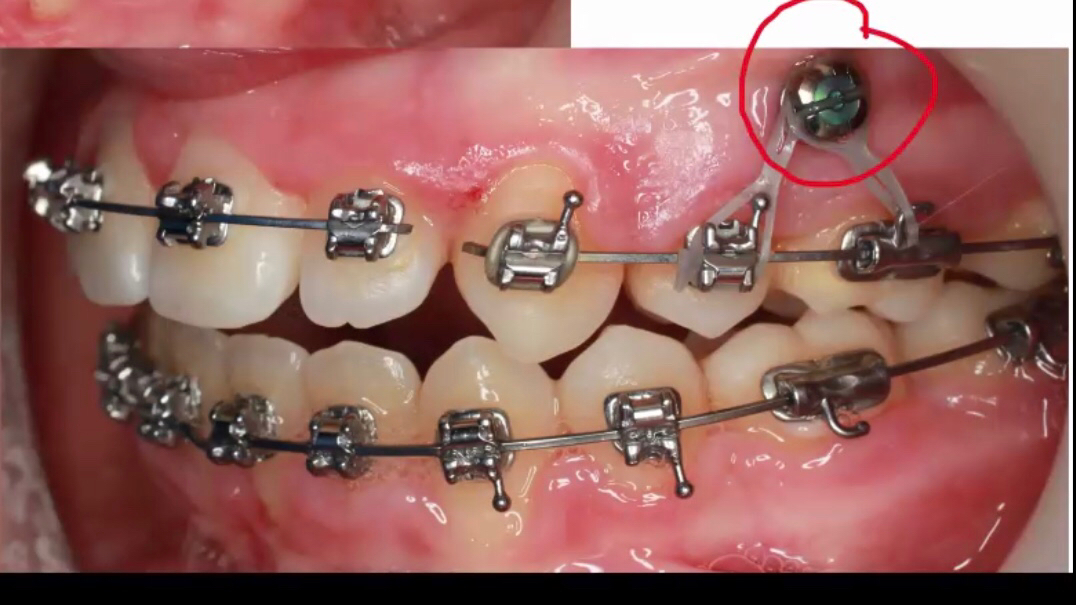

而要随心所欲移动牙齿且不产生副作用,很多时候就必须依靠牙齿以外的施力点,发挥这一重要作用的就是支抗钉,学名“暂时性支抗装置”(temporary anchorage device, TAD),是由纯钛或不锈钢制作的特殊的微小骨钉。

它长得和普通的钉子很像,但体积很小,一般长度6mm~12mm不等,直径1.5mm左右,是植入牙槽骨的临时性迷你植体。

在支抗植入后,通常情况下医生会增加牵引装置,加速牙齿的移动。